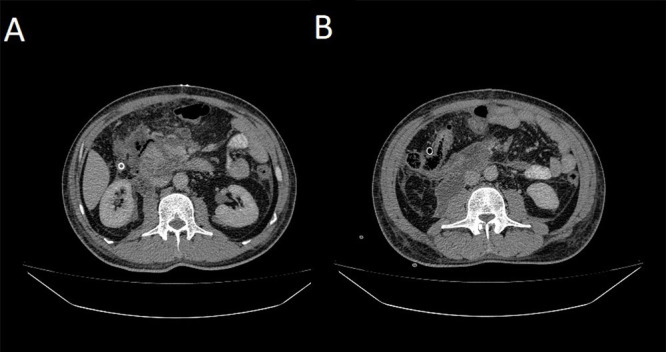

Abstract Image